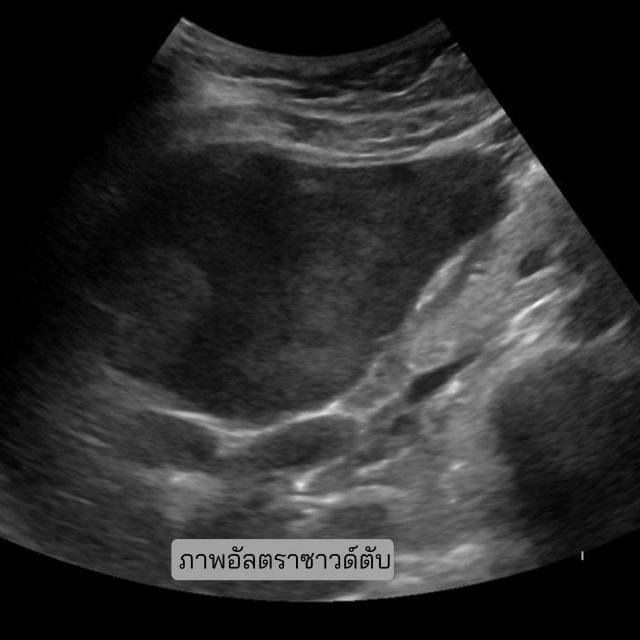

SmartLiva ทำงานโดยอัปเกรดภาพอัลตราซาวด์ขาวดำธรรมดา อัปโหลดผ่านเว็บได้ทั้งบนคอมพิวเตอร์หรือแท็บเล็ต ระบบจะปรับภาพให้ชัด คัดเฉพาะบริเวณเนื้อตับที่ต้องวิเคราะห์ ทำให้ภาพดูเข้าใจง่ายขึ้น ด้วยการไฮไลต์เป็นสี (เช่น ตับเป็นสีแดง ไขมันเป็นสีเหลือง) เพื่อเห็นความผิดปกติได้ทันที AI จะประเมิน 3 เรื่องพร้อมกัน คือ ระดับพังผืด/ความแข็งของตับ (F0–F4), ตรวจหาความผิดปกติของเนื้อเยื่อ เช่นถุงน้ำหรือมะเร็งตับ ตรวจหาพยาธิใบไม้ตับ ทั้งประมวล วิเคราะห์ สรุปผลออกเป็นรายงานพร้อมภาพประกอบและคำอธิบายที่คนทั่วไปเข้าใจได้